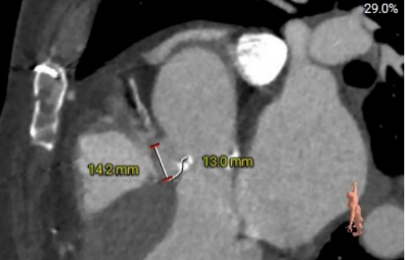

术前主动脉CTA评估:主动脉瓣二叶式type1型,L-R融合,瓣叶增厚、黏连,瓣叶游离缘、根部及融合脊中-重度钙化;主动脉瓣环周长折算直径约25.2mm;双侧冠脉开口高度可;双冠分支轻度钙化;术中建议造影角度LAO:9°,CRA:11°;左室流出道稍凸出;主动脉弓及降主动脉多发钙化,腹主动脉重度钙化。

瓣环:25.2mm

瓣上2mm:24.3mm

瓣上4mm:20.2mm

瓣上6mm:16.8mm

窦管交界:28.7mm

LVOT:25.5mm

升主动脉大小:40.5mm

左冠高度:12.8mm

右冠高度:16.4mm

左冠瓣叶长度:17.8mm

右冠瓣叶长度:13.0mm